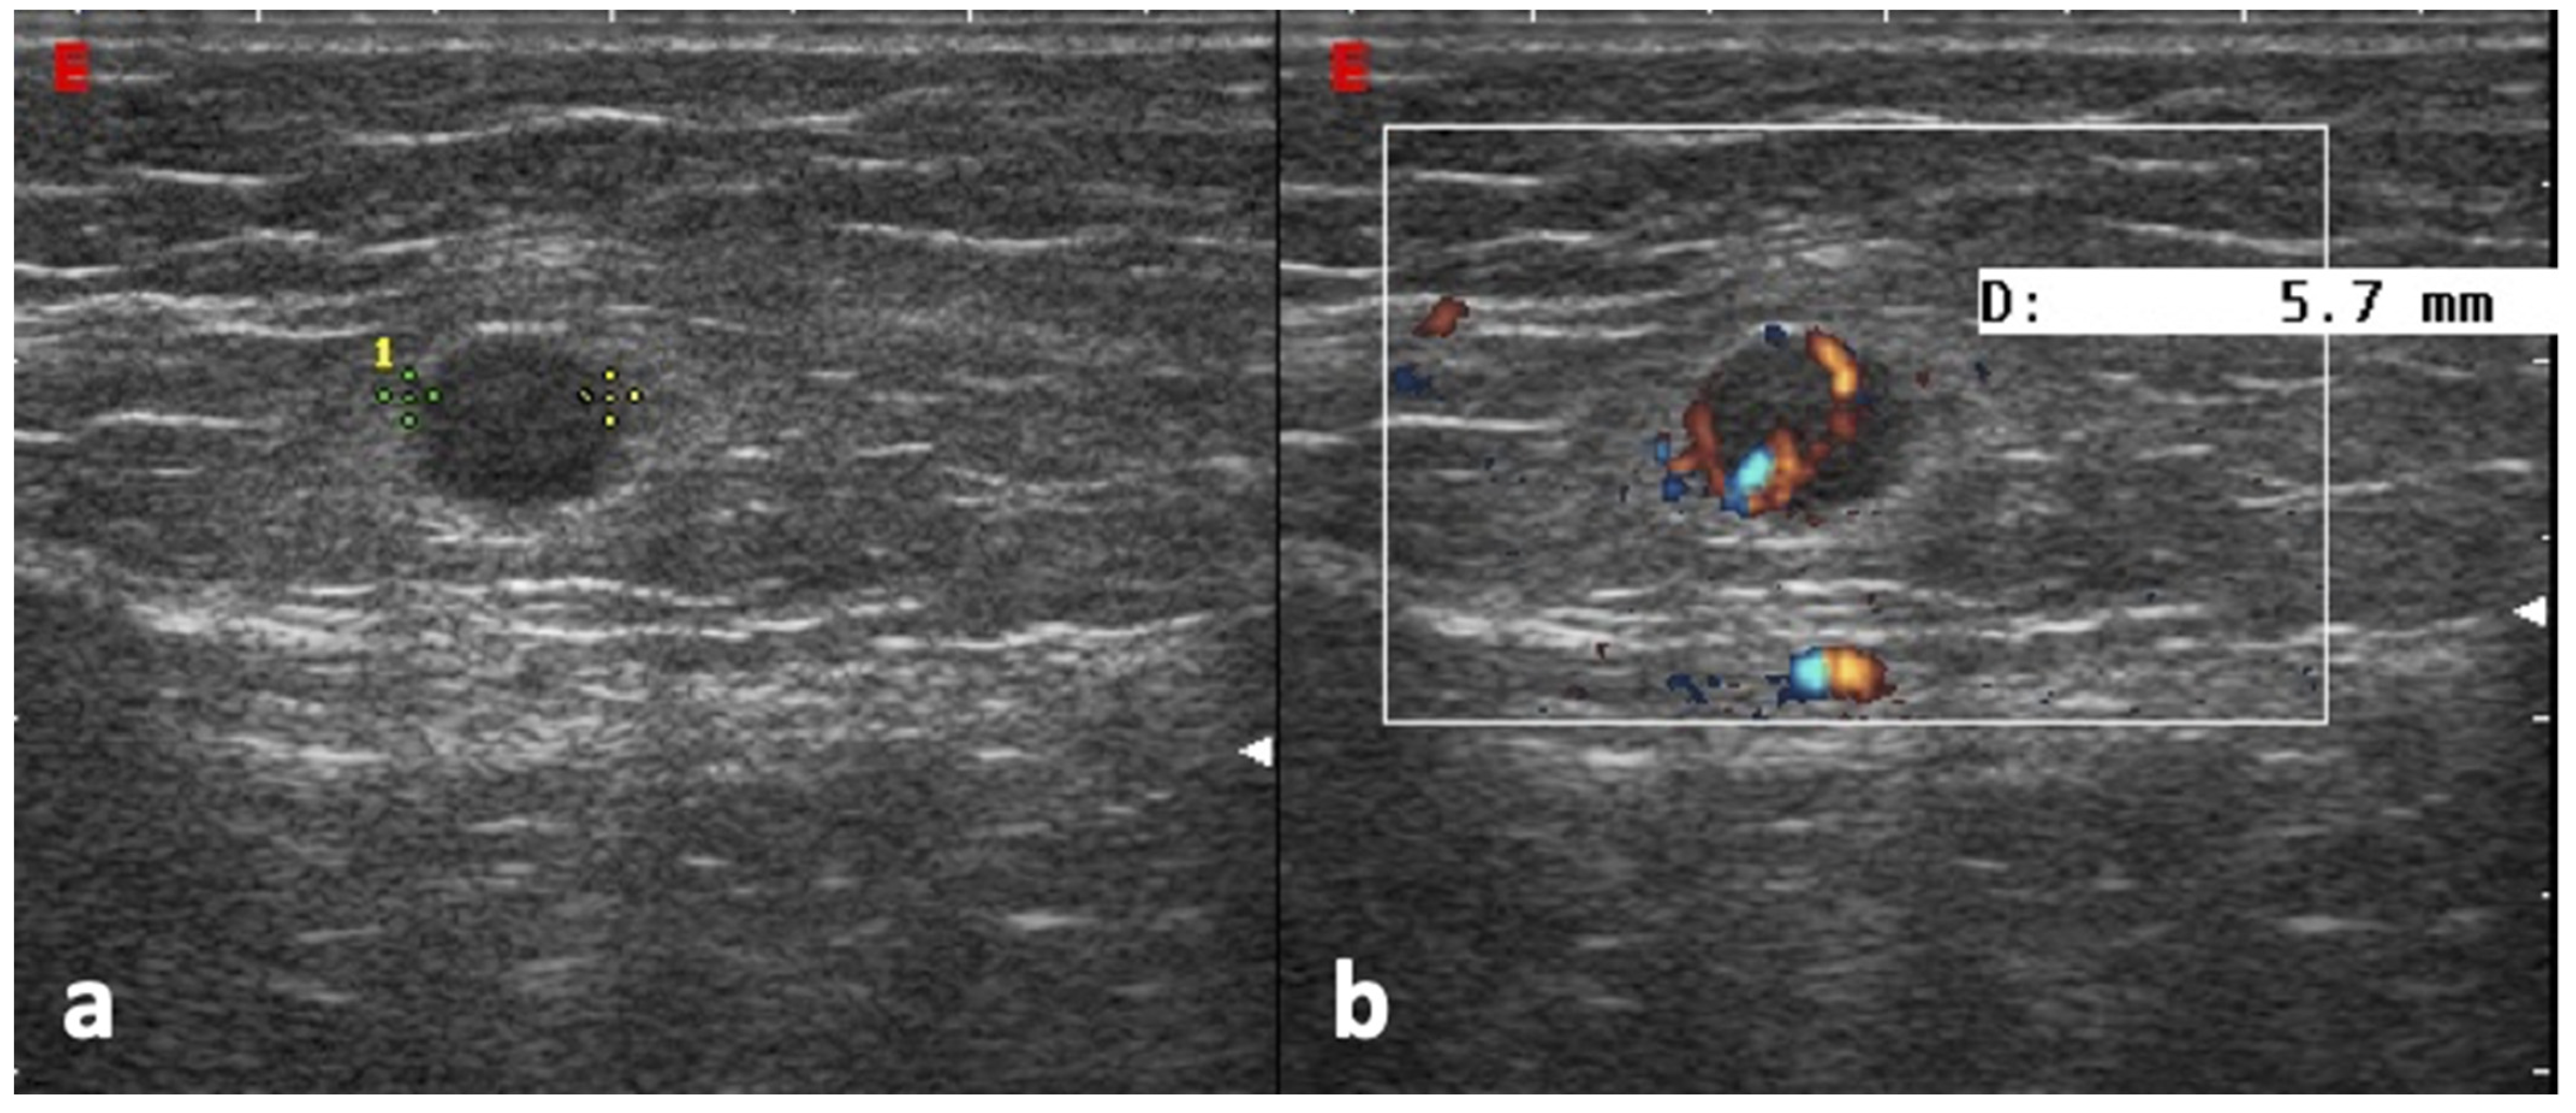

2.4. Ultrasound Assessment